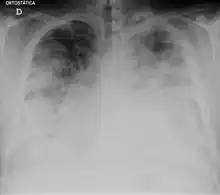

| Chest X-ray of a severe case of legionellosis upon admission to the emergency department | |

Laboratory tests may show that kidney functions, liver functions, and electrolyte levels are abnormal, which may include low sodium in the blood. Chest X-rays often show pneumonia with consolidation in the bottom portion of both lungs. Distinguishing Legionnaires' disease from other types of pneumonia by symptoms or radiologic findings alone is difficult; other tests are required for definitive diagnosis.